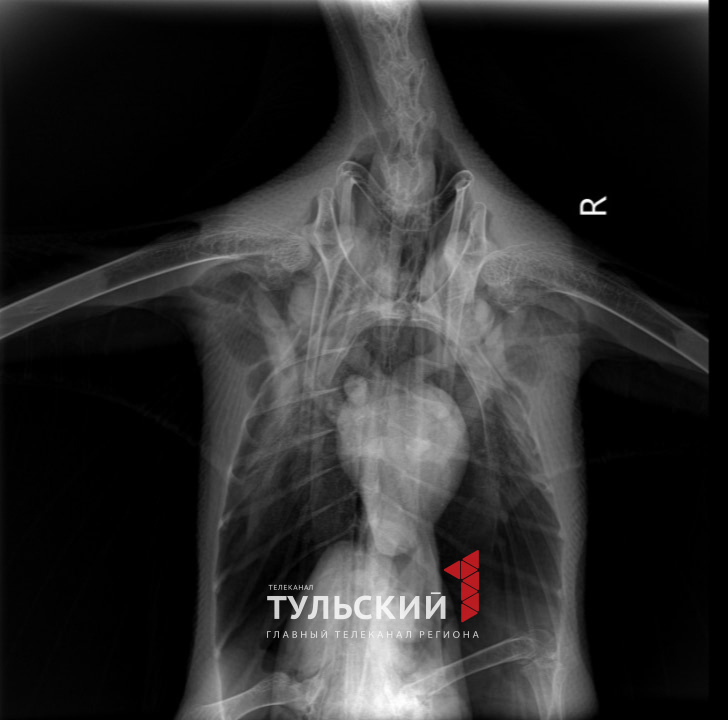

Вторый пернатый также получил множественные травмы, вероятно, из-за падения. У Тугдже оказались смещены кости черепа, сломан коракоидно-грудной сустав, а также несколько грудных и шейных позвонков. Кроме того, есть подозрение на перелом крестца.

У птицы искривлены хвост и крылья, при ходьбе лебедь слегка заваливается. Началась пневмония. Сломанные грудные позвонки давят на воздушные мешки, сдавливая желудок и кишечник, поэтому есть пока Тугдже плохо.

Чтобы выяснить это птице дважды делали рентген. Сейчас ситуация нестабильная, но ветеринары говорят, если удастся остановить инфекции и сломанные позвонки не сместятся, есть шанс на хороший исход: Тугдже сможет жить в неволе.